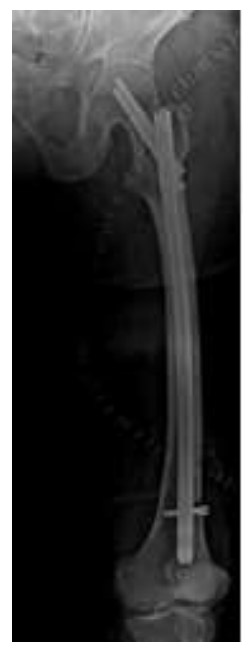

Ameliyat Sonrası: Röntgende uygulanan intramedüller çivi görülmekte